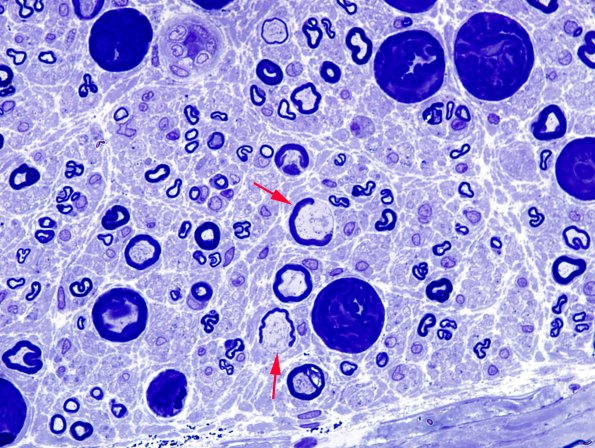

Washington University Experience | PERIPHERAL NEUROPATHY | 0 PNS ARTIFACTS | 16A4 Artifacts, crush & vesicular myelin Plastic 6 copy.jpg

The mysterious artifact (arrows) looks like it must involve herniation of the axoplasm through/around the myelin sheath. (Toluidine blue stained one micron thick plastic embedded sections)